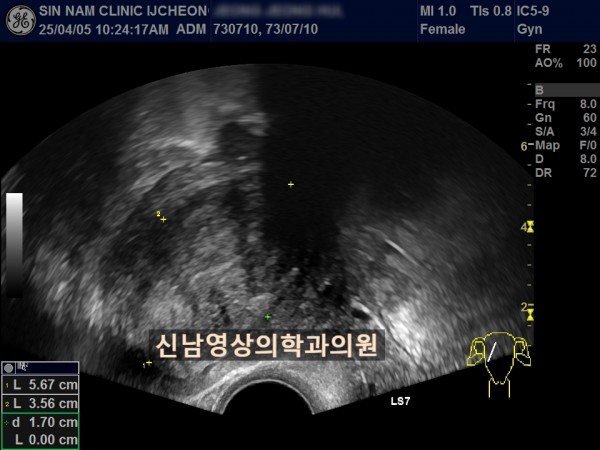

연령 : 52세

하복부 통증으로 내원하셨고, 초음파 검사상 자궁선근종과 난소낭종이 발견되었고, 난소암 혈액검사를 진행했습니다.

난소암 혈액검사 결과는 정상범위로 약간 높은 수치였기에 생리 끝나고, 다시 추적검사를 진행하기로 했지만 복통이 심해져 수술 진행했고, 수술장에서는 암의 가능성이 없는 것으로 전달 받았으나 최종 조직검사상 난소암으로 진단되었습니다.

여성들의 경우 난소 내막종에서 난소암으로 진행될 위험이 있고, 자궁선근종이 있는 분들은 난소내막종이 동반될 가능성도 높기 때문에 주기적으로 추적검사가 필요하고, 난소암 혈액검사와 초음파상 혹의 모양을 종합적으로 판단해 수술결정을 하게 됩니다.

난소낭종의 문제는 혹의 꼬이면서(염좌) 복막염으로 진행될 위험이 있다는 것입니다.

난소혹의 형태가 애매할 경우에는 생리직후에 추적검사로 형태 변화가 있는지를 관찰하는 것이 필요합니다.